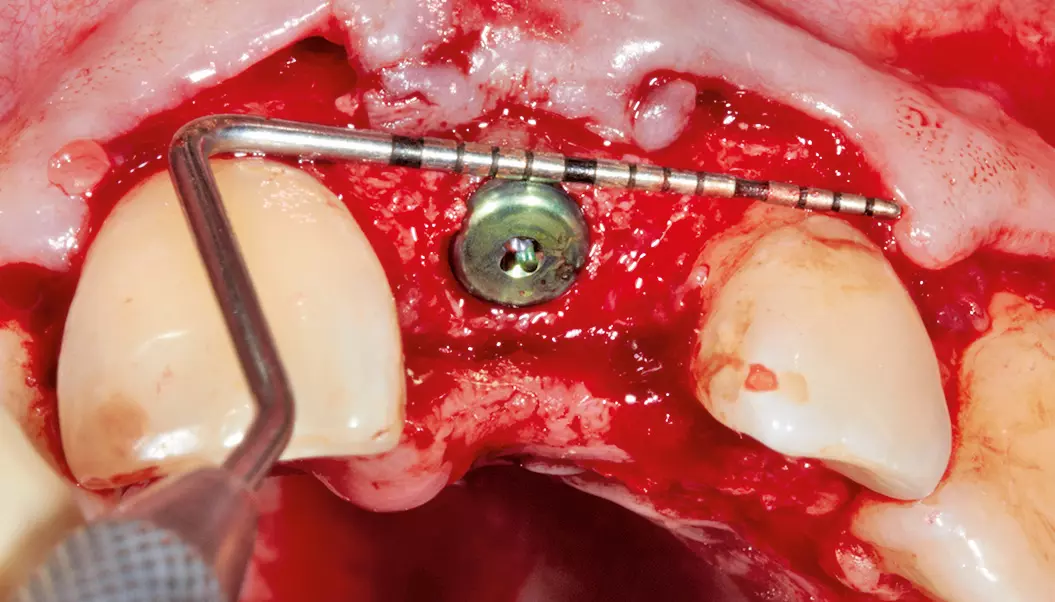

Nach einer Einheilphase von drei Monaten konnte implantiert werden. Es sollte eine okklusal verschraubte Krone verwendet werden. Die Entscheidung des Implantatsystems fiel auf ein ELEMENT Implantat von Thommen Medical, da es über einen sehr kleinen Schraubenkanal verfügt und damit eine gute prothetische Versorgung – gerade im Frontzahnbereich – ermöglicht. Hier hat man es häufig mit Problemen der Einschubrichtung des Implantates zu tun und ein kleiner Schraubendurchmesser schafft Platz, um eine Verschraubung möglich zu machen. Für die Implantation erfolgte in Lokalanästhesie eine krestale, leicht lingual versetzte Schnittführung unter Erhaltung eines einige Millimeter breiten Streifens befestigter Mukosa. Das Implantat wurde in korrekter Position ca. 3-4 mm oberhalb der Schmelz-Zement-Grenze sowie ca. 2 mm oral von der Verbindungslinie der benachbarten Wurzeloberflächen und mit einer Implantatachse palatinal von der geplanten Schneidekante gesetzt (Abb. 7 und 8). Danach wurde ein steriler Abformpfosten für eine offene Abformung aufgeschraubt. Zur Anfertigung des Index wurde Triad Gel (Triad Gel Clear Colorless, Dentsply International, York, PA, USA) benutzt. Dazu wurde das Material in eine sterile 2-ml-Einmal-Spritze gefüllt und auf den Abformpfosten und beide Nachbarzähne aufgetragen. Die Aushärtung erfolgte mit einer in eine sterile Folie eingepackten Polymerisationslampe.